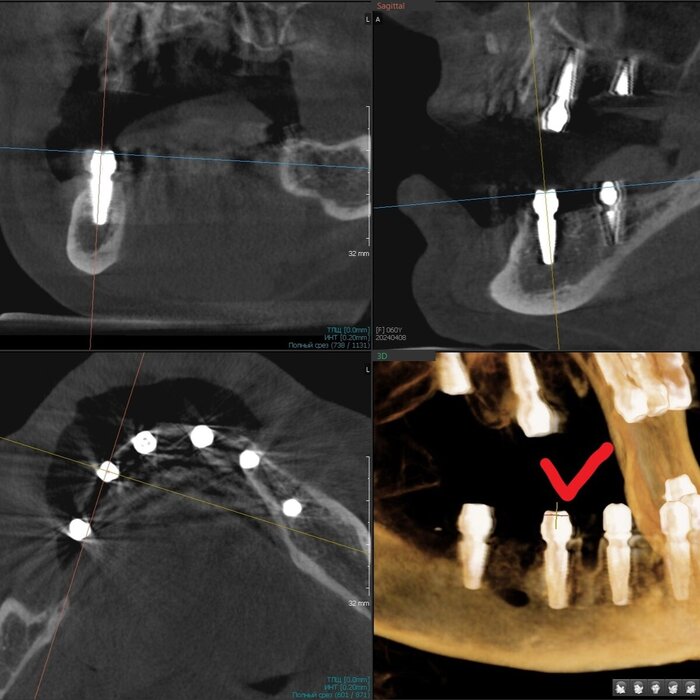

Получилось так, что сверху всего 8 зубов, по 4 с каждой стороны. Чёрная точка (которую вы точно увидите, скос эмали на зубе 1.1) - конструктивные особенности, всё это будет закрыто пломбировочным материалом. Зуб 1.1 - дополнительный имлантат, который потом планируем убрать. Он нужен лишь для усиления, ибо торк полноценный был получен только на одном из остальных 6-ти установленных.

Напоминаю - протезы временные адаптационные

Так же важный момент - верхний протез соприкасается с нижним только в точках полученного торка (их всего 2), остальное "на весу" и жевать не способно.

Рекомендации - мягкая, жидкая пища 4 месяца! Это важно.

Низ - всё ок.